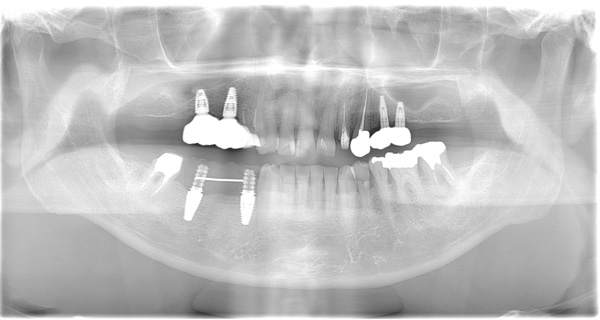

| 年代・性別 | 50代 女性 |

|---|---|

| 主訴 | 左上のブリッジがグラグラして外れそう |

| 治療期間 | 約18ヶ月 |

| 費用 | 1,600,000円 |

| 治療内容 | インプラント、骨造成、サイナスリフト、セラミック修復 |

| 治療に伴うリスク | インプラント周囲炎 セラミックの破折、脱離 |